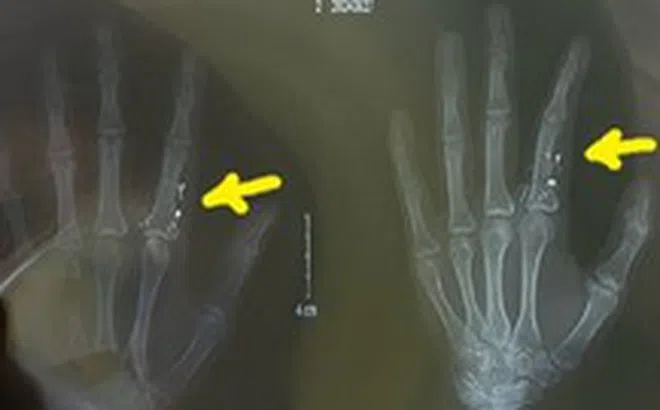

Sau khi bị đầu chứa thủy ngân của nhiệt kế vỡ, chọc mạnh vào ngón trỏ bàn tay trái, bệnh nhân chủ quan không đi kiểm tra. Khi thấy ngón tay sưng mủ áp xe, bệnh nhân mới đến bệnh viện để thăm khám.